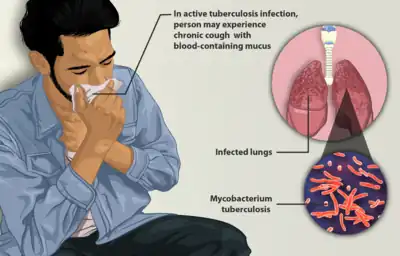

Tuberculosis (TB), also known colloquially as the "white death", or historically as consumption,[7] is an infectious disease usually caused by Mycobacterium tuberculosis (MTB) bacteria.[1] Tuberculosis generally affects the lungs, but it can also affect other parts of the body.[1] Most infections show no symptoms, in which case it is known as latent tuberculosis.[1] Around 10% of latent infections progress to active disease which, if left untreated, kill about half of those affected.[1] Typical symptoms of active TB are chronic cough with blood-containing mucus, fever, night sweats, and weight loss.[1] Infection of other organs can cause a wide range of symptoms.[8]

Tuberculosis may infect any part of the body, but most commonly occurs in the lungs (known as pulmonary tuberculosis).[8] Extrapulmonary TB occurs when tuberculosis develops outside of the lungs, although extrapulmonary TB may coexist with pulmonary TB.[8]

General signs and symptoms include fever, chills, night sweats, loss of appetite, weight loss, and fatigue.[8] Significant nail clubbing may also occur.[17]

If a tuberculosis infection does become active, it most commonly involves the lungs (in about 90% of cases).[15][18] Symptoms may include chest pain and a prolonged cough producing sputum. About 25% of people may not have any symptoms (i.e., they remain asymptomatic).[15] Occasionally, people may cough up blood in small amounts, and in very rare cases, the infection may erode into the pulmonary artery or a Rasmussen's aneurysm, resulting in massive bleeding.[8][19] Tuberculosis may become a chronic illness and cause extensive scarring in the upper lobes of the lungs. The upper lung lobes are more frequently affected by tuberculosis than the lower ones.[8] The reason for this difference is not clear.[14] It may be due to either better air flow,[14] or poor lymph drainage within the upper lungs.[8]

Extrapulmonary

In 15–20% of active cases, the infection spreads outside the lungs, causing other kinds of TB.[20] These are collectively denoted as extrapulmonary tuberculosis.[21] Extrapulmonary TB occurs more commonly in people with a weakened immune system and young children. In those with HIV, this occurs in more than 50% of cases.[21] Notable extrapulmonary infection sites include the pleura (in tuberculous pleurisy), the central nervous system (in tuberculous meningitis), the lymphatic system (in scrofula of the neck), the genitourinary system (in urogenital tuberculosis), and the bones and joints (in Pott disease of the spine), among others. A potentially more serious, widespread form of TB is called "disseminated tuberculosis"; it is also known as miliary tuberculosis.[8] Miliary TB currently makes up about 10% of extrapulmonary cases.[22]